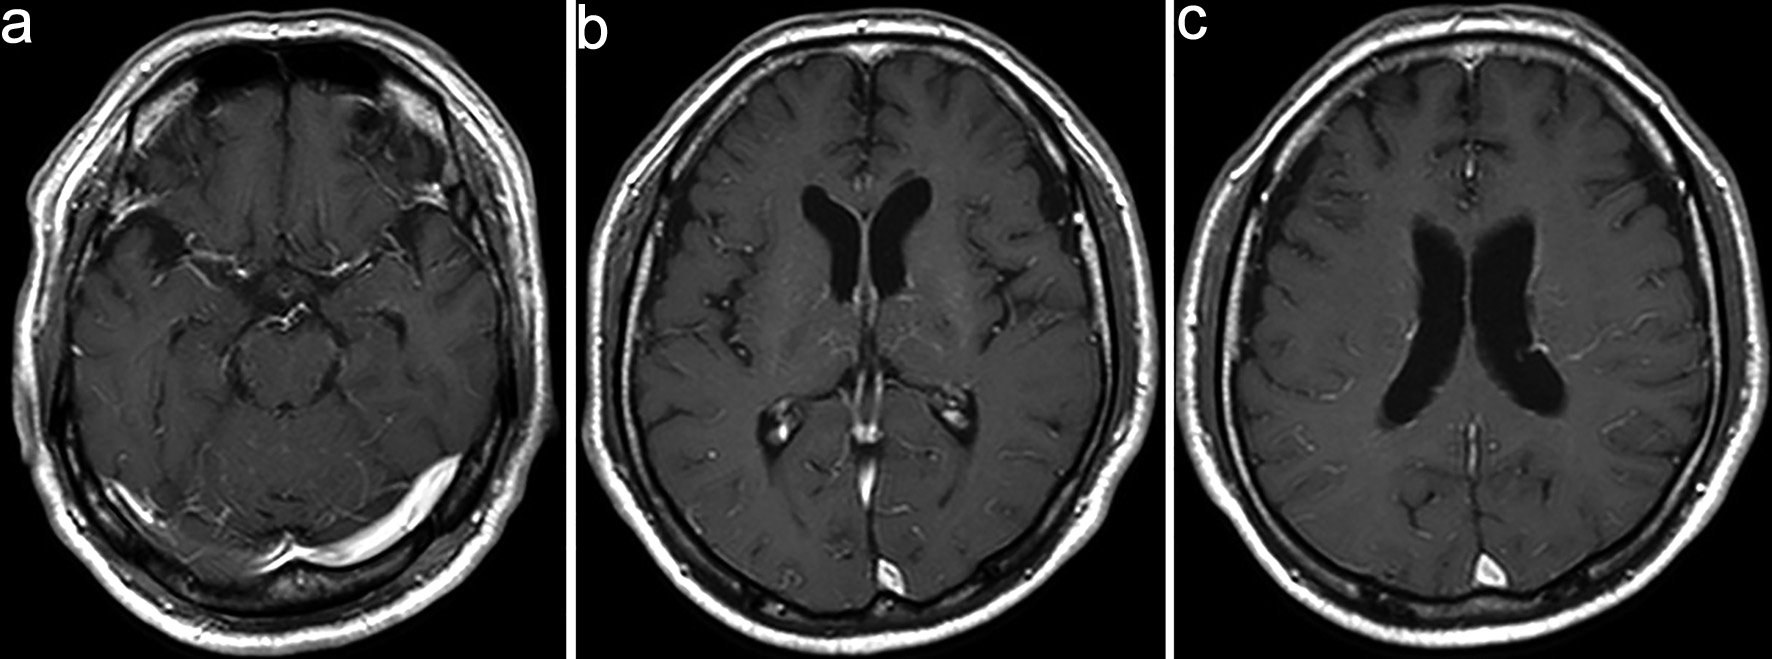

Although the positive results for anti-MOG antibodies led us to consider MOGAD as the initial diagnosis, the patient’s clinical course, including progressive impairment of consciousness and hyponatremia, was atypical. Serial follow-up MRI (DWI) revealed new small hyperintense lesions appearing sequentially in the left corona radiata and near the occipital horn of the left lateral ventricle (Fig. 2). On day 11, contrast-enhanced MRI showed serpiginous perivascular enhancement in the basal ganglia along with leptomeningeal enhancement (Fig. 3); however, these findings were not clearly consistent with the typical radial periventricular enhancement pattern reported in GFAP astrocytopathy. Given these atypical clinical and radiological findings, additional autoimmune antibody testing was performed, which confirmed the presence of anti-GFAPα antibodies in the CSF (Cell-based assay). Spinal cord imaging was performed and revealed no abnormalities. The patient had no visual symptoms, including visual disturbance, ocular pain, or visual field impairment. Dedicated optic nerve MRI was not obtained; however, the patient was evaluated by ophthalmology, which identified perivascular inflammation around the right optic nerve. Whole-body computed tomography (CT) screening and tumor markers revealed no malignancy.

Click for large image

Figure 2. Serial diffusion-weighted imaging (DWI) showing the appearance of new lesions. (a–c) Follow-up magnetic resonance imaging (MRI) on day 7 (a), day 20 (b), and day 35 (c) shows small hyperintense lesions appearing sequentially in the left corona radiata and near the occipital left horn of the lateral ventricle. (d–f) Corresponding fluid-attenuated inversion recovery (FLAIR) images acquired at the same time points (a–d, b–e, and c–f pairs) demonstrate hyperintense white matter lesions.

Figure 3. Contrast-enhanced magnetic resonance imaging (MRI) on day 11. (a–c) Contrast-enhanced MRI shows serpiginous perivascular enhancement in the basal ganglia along with leptomeningeal enhancement.